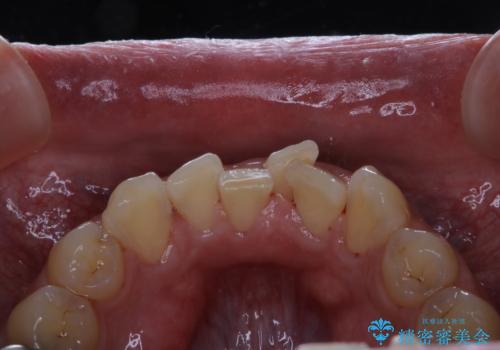

前歯メインにステインの付着が見られ、コース内容を相談した結果PMTC(保険外治療)の30分コースを行いました。

また、今後矯正治療を検討しているとのことだったので次回、矯正治療の無料カウンセリングをご案内しました。